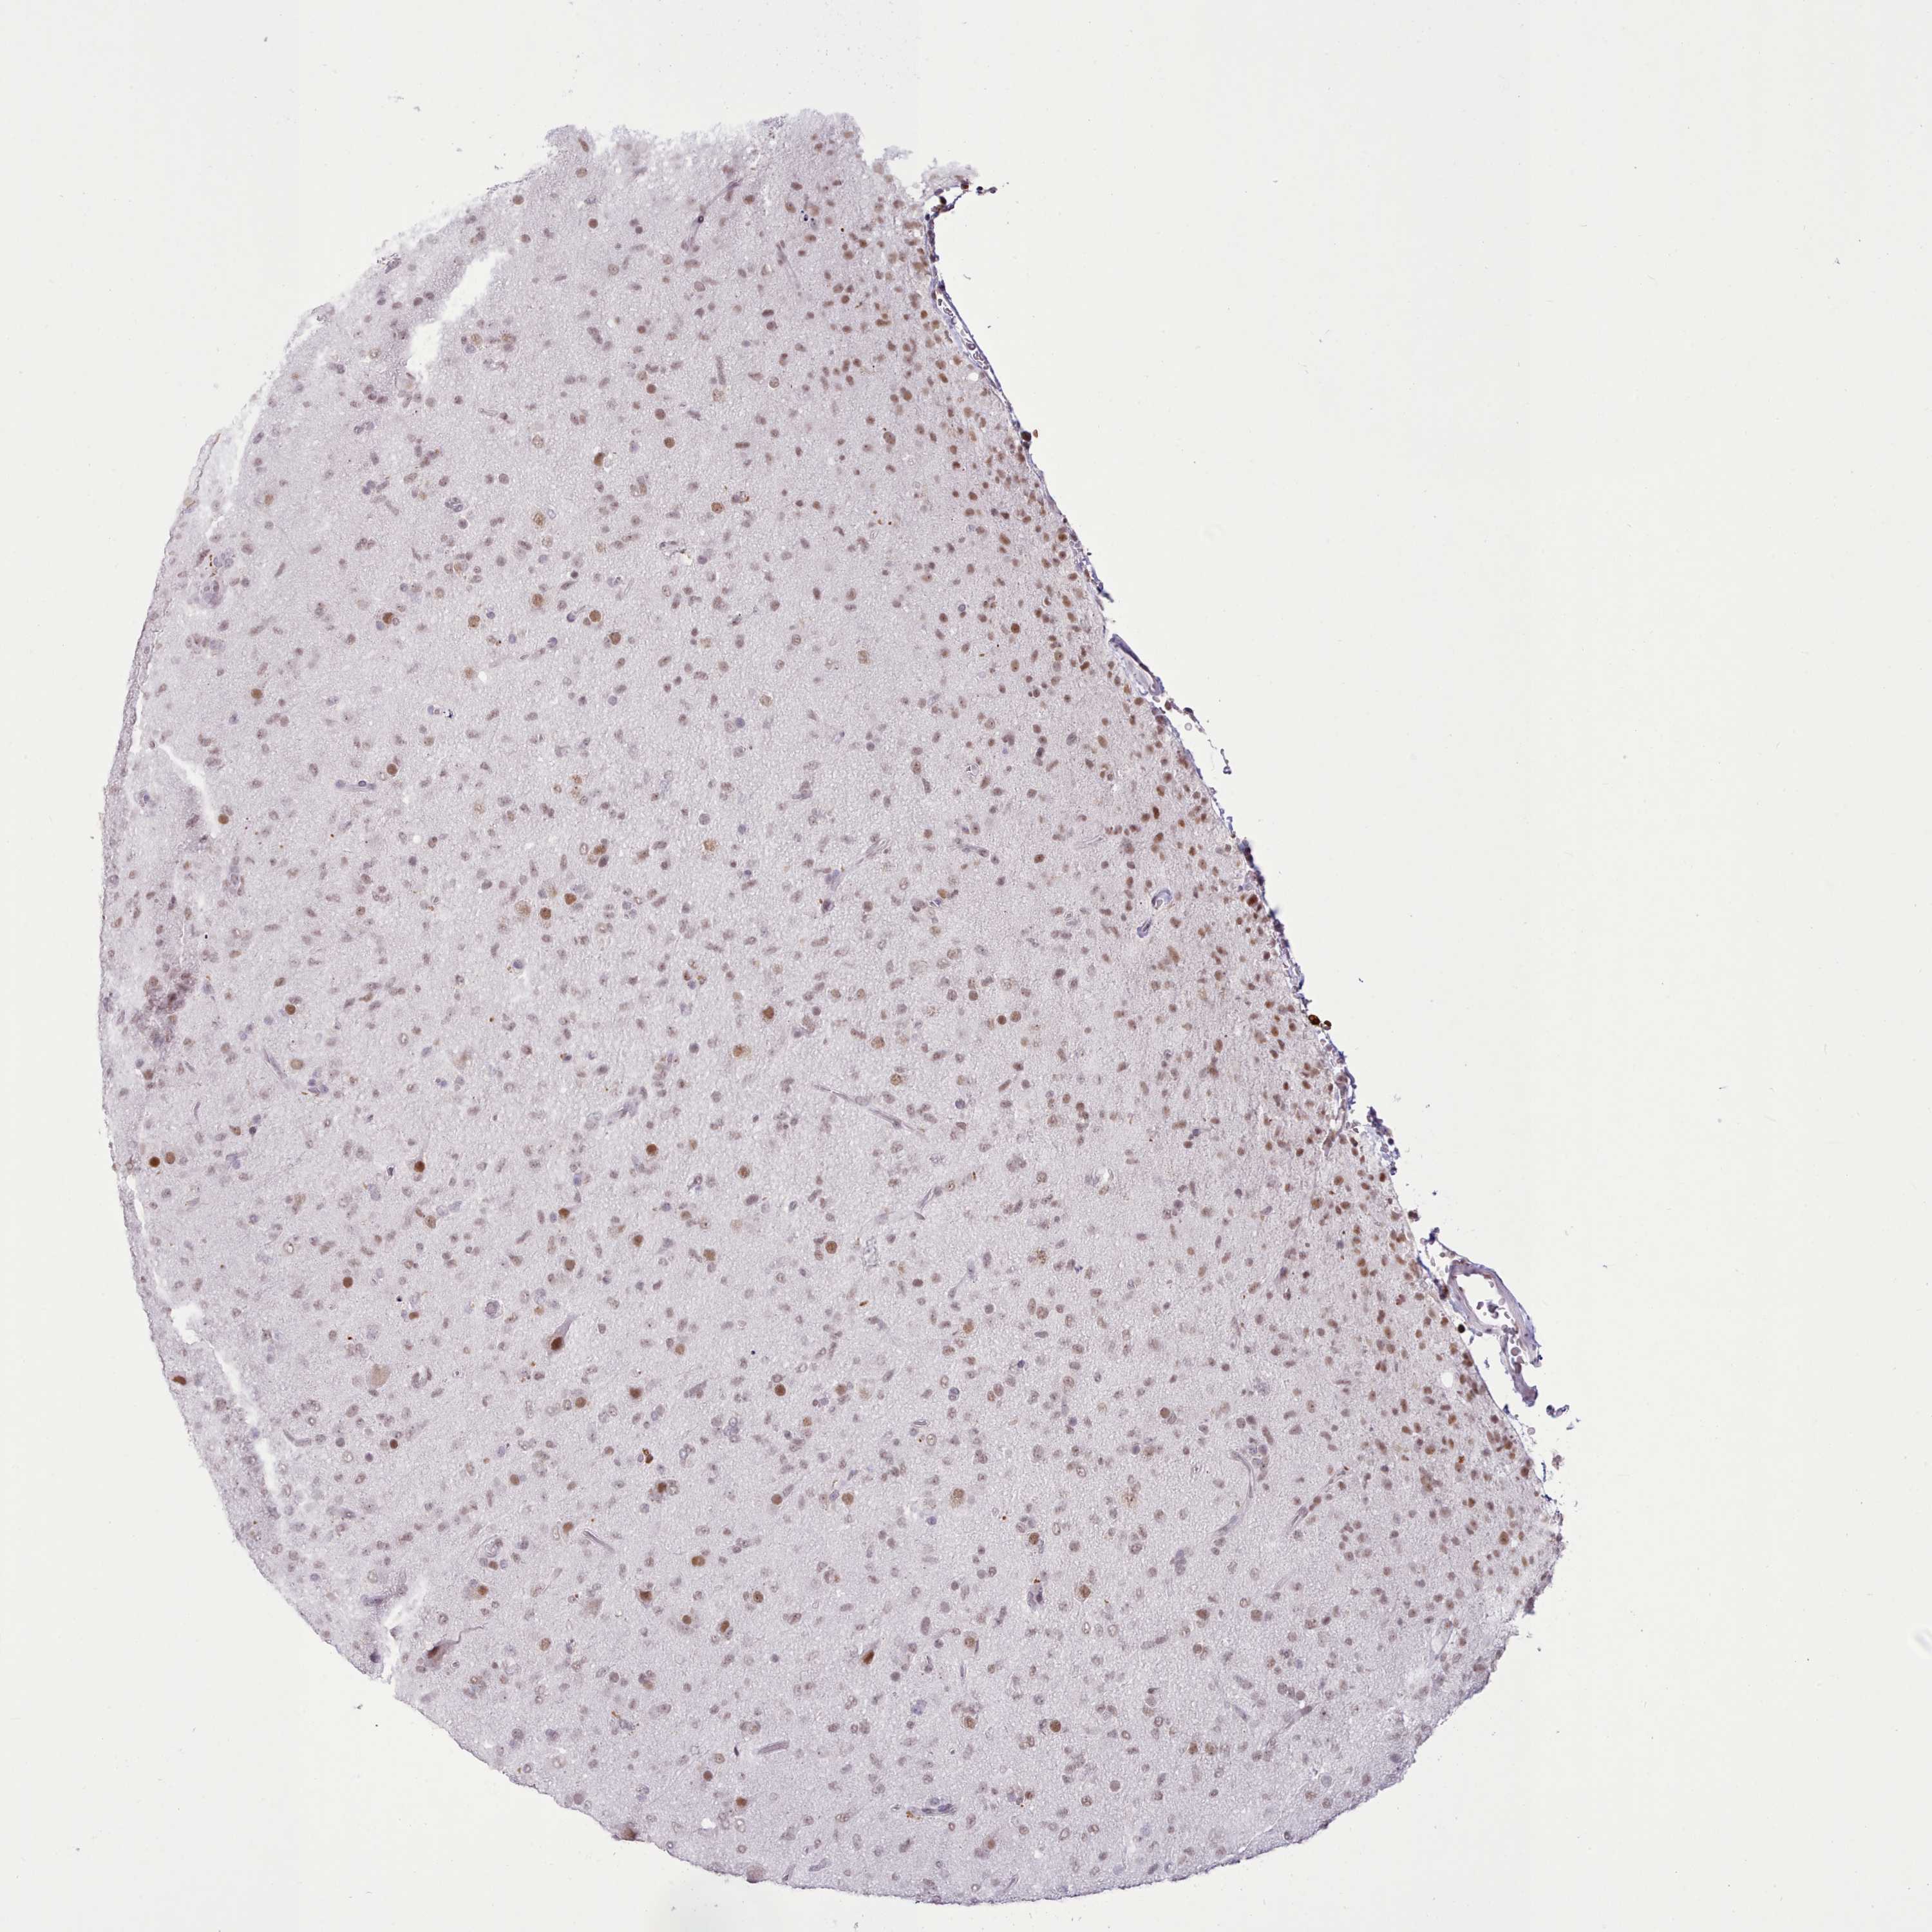

GLIOMA - Protein expressioni

A mouse-over function shows sample information and annotation data. Click on an image to view it in a full screen mode. Samples can be filtered based on level of antibody staining by selecting one or several of the following categories: high, medium, low and not detected. The assay and annotation is described here.

Note that samples used for immunohistochemistry by the Human Protein Atlas do not correspond to samples in the TCGA dataset.

Antibody stainingi

Antibody staining in the annotated cell types in the current human tissue is reported as not detected, low, medium, or high, based on conventional immunohistochemistry profiling in selected tissues. This score is based on the combination of the staining intensity and fraction of stained cells.

Each image is clickable and will lead to virtual microscopy that enables deeper exploration of all samples and also displays staining intensity scores, fraction scores and subcellular localization as well as patient and tissue information for each sample.

Antibody HPA052059

Staining

High

Medium

Low

Not detected

Intensity

Strong

Moderate

Weak

Negative

Quantity

>75%

75%-25%

<25%

None

Location

Nuclear

Cytoplasmic/membranous

Cytoplasmic/membranous,nuclear

Glioma, malignant, Low grade

Glioma, malignant, High grade